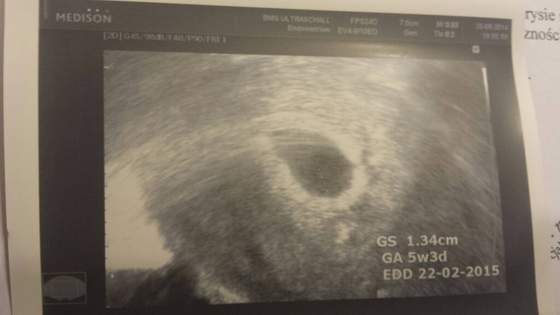

No dziwczyny ja tam z rana jak siknelam to nic nie widzialam a on mi fote przeslal na maila i nawet widac. Za 30 min bede w domu to postaram sie siasc na tablecie i spprobowac wam przeslac bo tak moja durna komora nie podola. A jak nie dzis to jutro z ranca dwa bo zasiade na kompie u rodzicow na dole. Ciekawe co jutro bedIe. Pretesta kupilam. Masakra ale jestem podjarana.... zeby tylko klopsa nie bylo